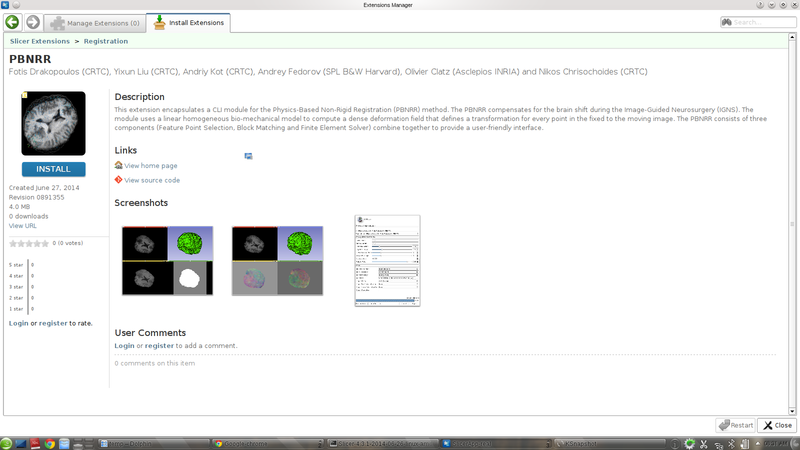

This project implements ITK's Physics-Based Non-Rigid Registration (PBNRR) method. The PBNRR compensates for the brain shifts during the Image-Guided Neurosurgery (IGNS). The method uses a linear homogeneous bio-mechanical model to compute a dense deformation field that defines a transformation for every point in the fixed image to the moving image. The PBNRR includes the following three components combine together to provide a user-friendly interface.

- Develop an extension that encapsulates a CLI module for the PBNRR method.

- The extension is available in the nightly build version of Slicer with name: PBNRR.

- The documentation page for the extension is available here: https://www.slicer.org/wiki/Documentation/Nightly/Extensions/PBNRR.